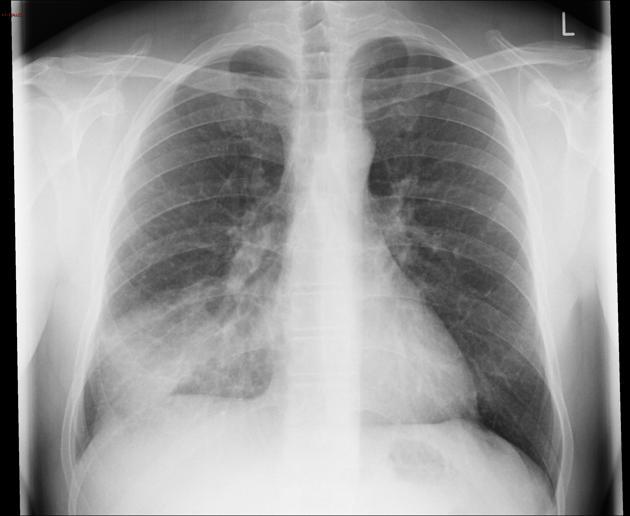

Comment on this CXR

Consolidation in the right middle lobe consistent with pneumonia